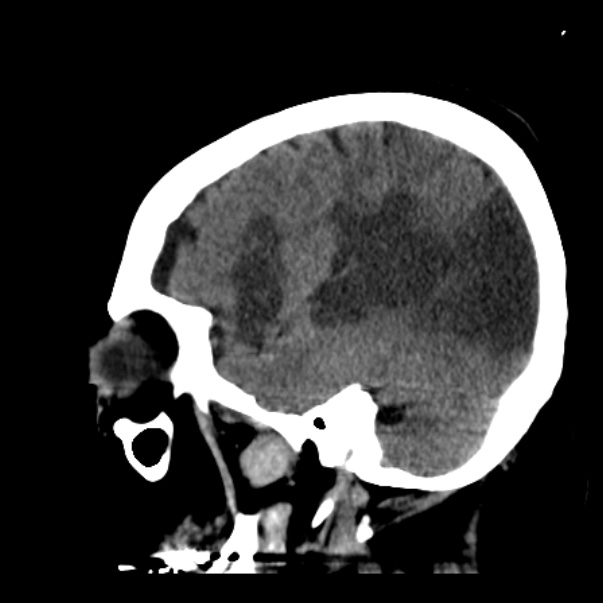

In this CT scan image of the brain there is a region which has sufferd from and acute infarction/stroke. Can you recognize the region? if you can can , which are the structures (nuclei, pathways) that are most likely affected by the lesion and what could be the possible neurological outcomes in this patient ?

View this question